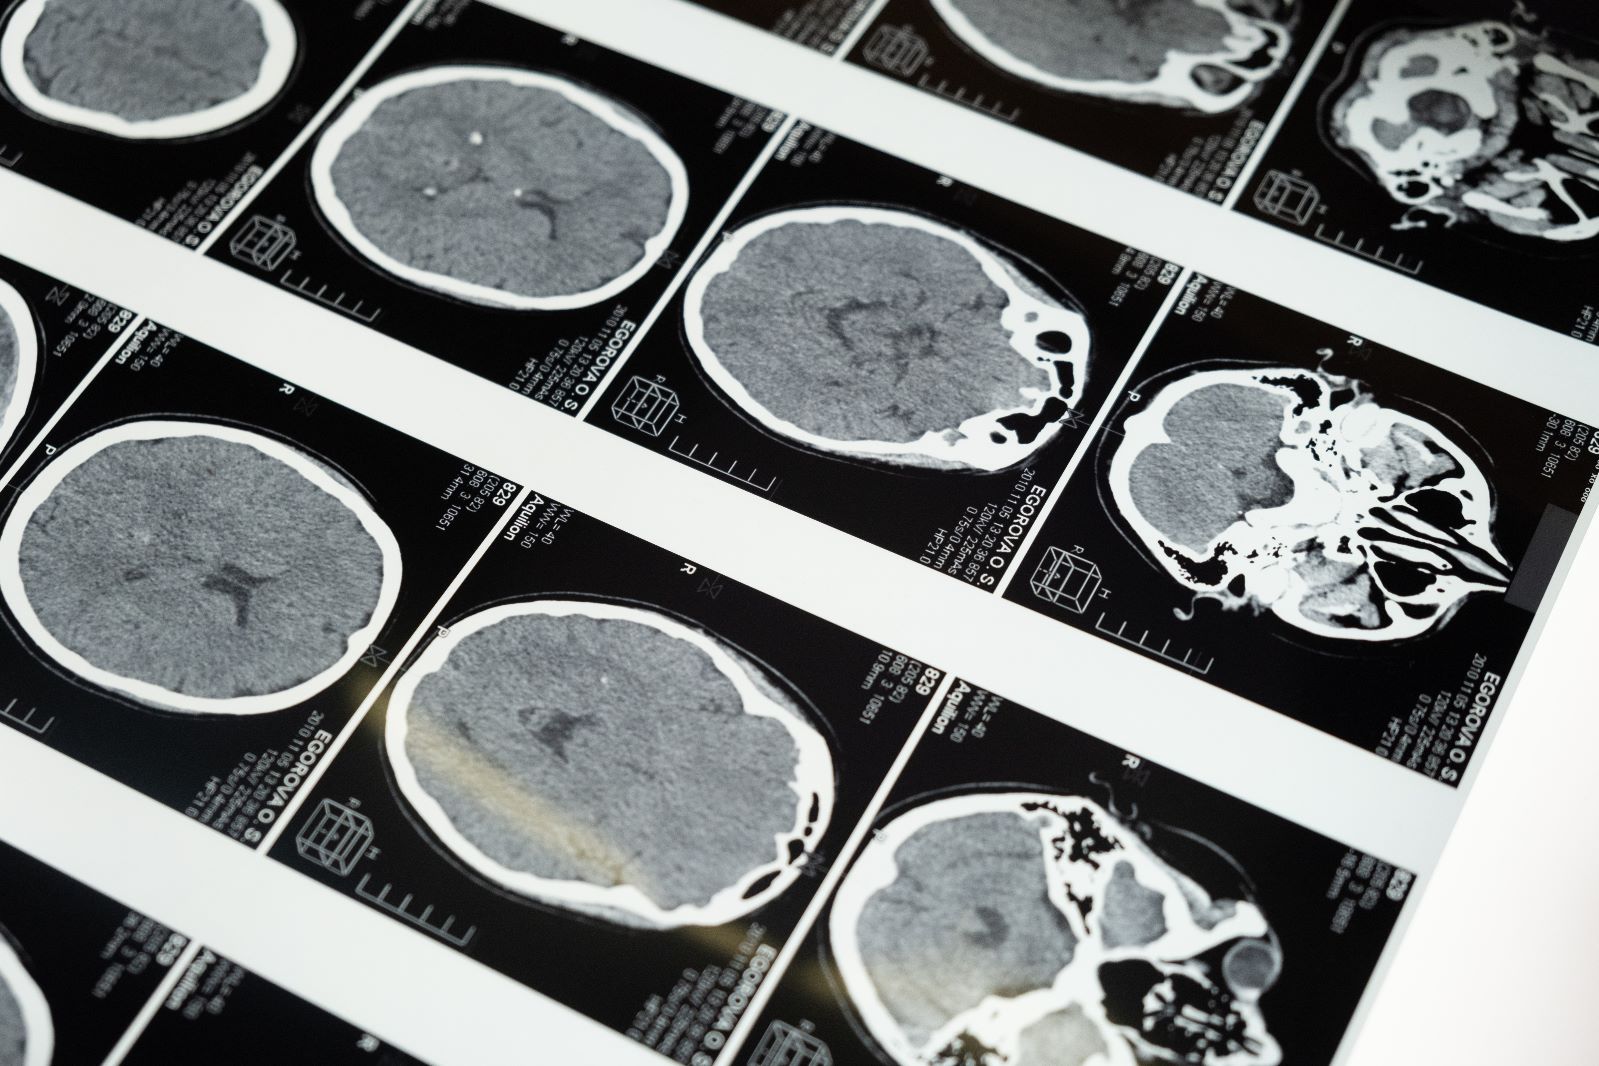

Bazı çalışma ve klinik deneylere dayanarak Alzheimer hastalığında “mucize” yaratan çözümün, günde sadece 4 çay kaşığı hindistancevizi yağı tüketmek olduğunu yazması, çok sayıda hasta ve hasta yakını için “Büyük bir umut” anlamına gelse de “Bu bir mucize” iddiası için erken olduğunu düşünenlerin sayısı da hiç az değil. Son yıllarda görüntüleme yöntemleri ve hastalığın erken tanısı konusunda ilerlemeler sağlanmakla birlikte Alzheimer hâlâ tedavisi olmayan bir hastalık. Peki konunun uzmanları hindistancevizi yağı konusunda ne düşünüyor? İşte yanıtlar...